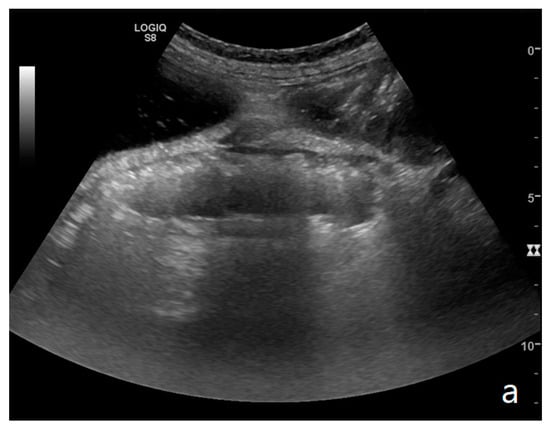

Figure 4.

A complicated SBO in a 69-year-old male with gastric cancer and peritoneal carcinosis. Ultrasound images show long (a) and axial (b) evaluations of a fluid-filled, dilated small bowel loop with hyperechogenic floating material (shown with an asterisk) (b,d). Bowel peristalsis was absent. Mild parietal and valvulae conniventes thickening are present (c,d). Downstream loops present normal caliber (bowel jump diameter). Free fluid is interposed between bowel loops (black arrow) (b).

Figure 5.

A complicated SBO presenting fluid-filled bowel loops with thickened walls with a stratified echo pattern (a) and thickened valvulae conniventes (b). Free fluid in the abdominal cavity was detected (b). Tail comet artifacts for air-fluid levels are visible (a). At the time of surgery, the bowel loop was necrotic.

The valvulae conniventes (Kerckring valves, circular folds) are permanent folds composed of mucosa and submucosa that project into the intestinal lumen and are clearly visible in the case of fluid distension (keyboard sign) [31]. At an early stage of SBO, it is not uncommon to see the valvulae in the upstream loop appearing more numerous and closer to each other. As the occlusive state continues, the loop upstream of the obstructive fulcrum becomes weaker, bowel walls appear thin, and the folds flatten (Figure 2a and Figure 3a,b). The upstream loops more distant from the obstructive fulcrum may still present peristalsis, albeit reduced and ineffective. In complicated ileus, with the onset of vascular loop distress, the walls and valvulae become thicker and weaker due to parietal edema and venous stasis, with possible dramatic parietal necrosis and subsequent perforation (Figure 4a–d and Figure 5a,b) [12,43].